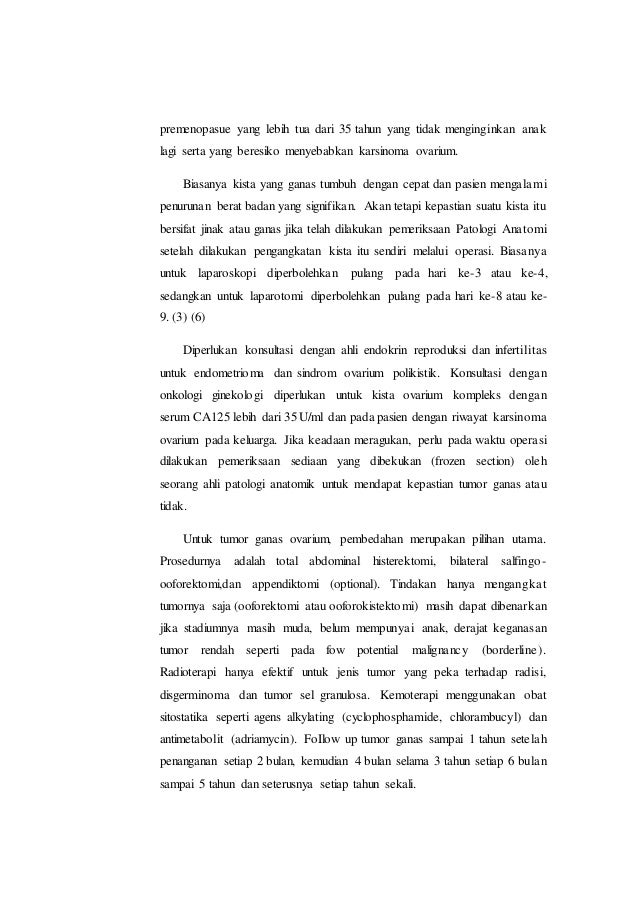

Lapsus Kista Ovarii - Apriamalia - [PDF Document]

Lapsus Kista Ovarii - Apriamalia - [PDF Document]

Cr kista ovarium fixxx

Cr kista ovarium fixxx